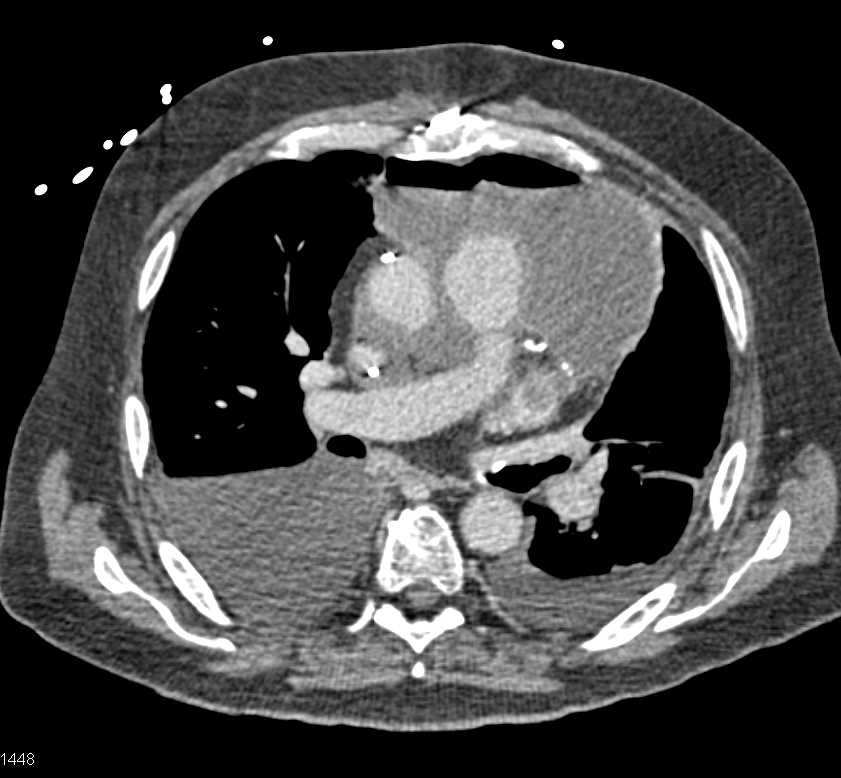

Post Cardiac Surgery Changes